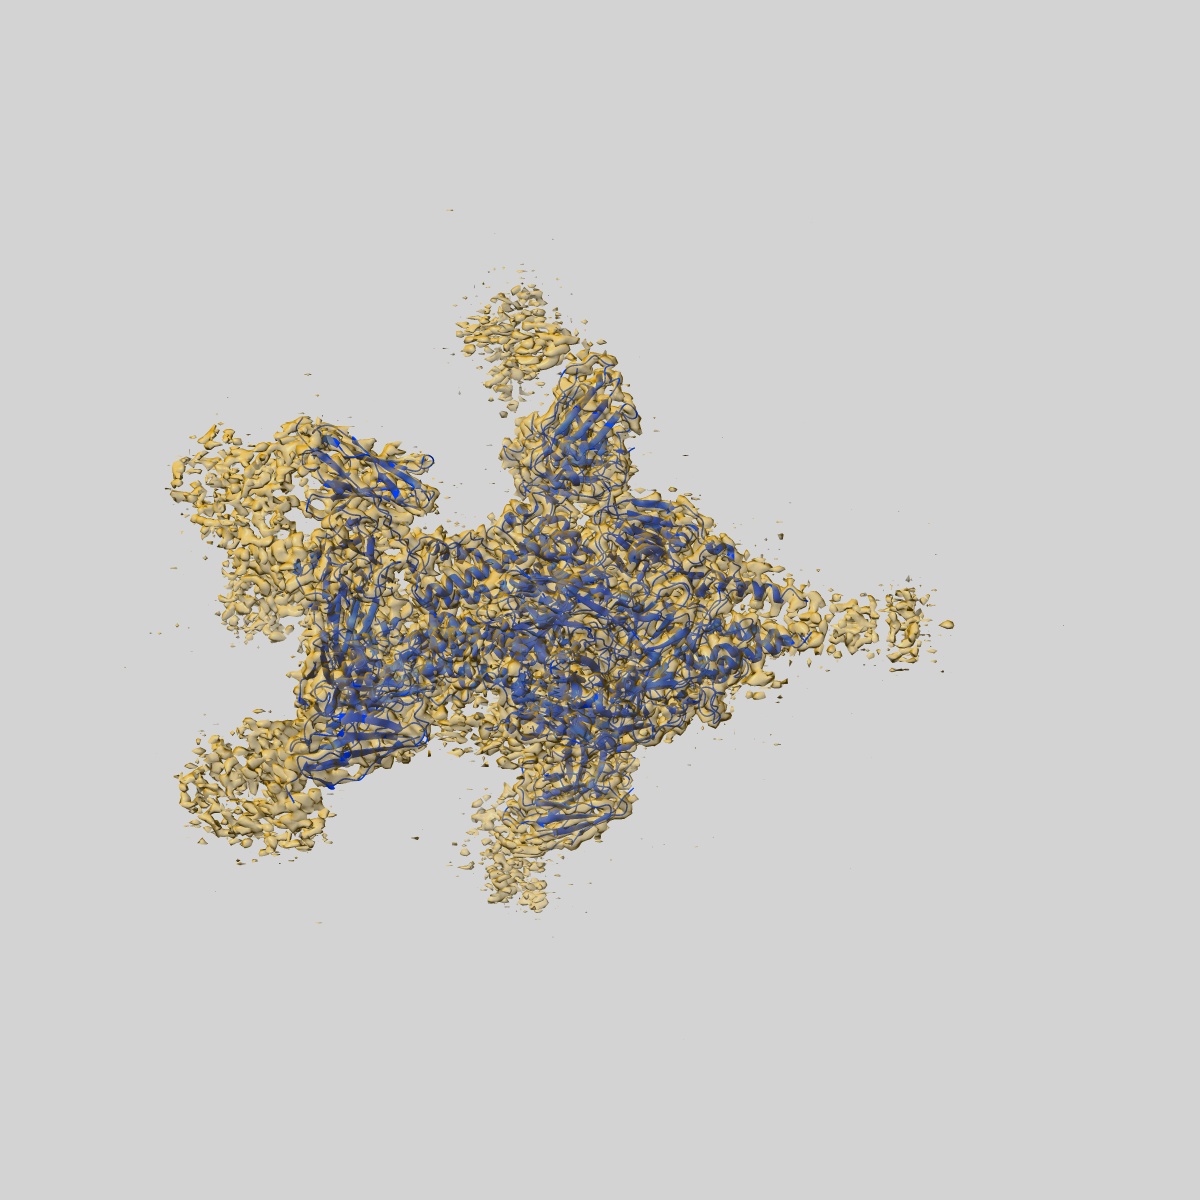

EMD-26562

Cryo-EM structure of Human respiratory syncytial virus F variant (construct pXCS847A)

Single-particle3.7 Å

Sample: Human respiratory syncytial virus F variant (construct pXCS847A) with Fabs AM14 and AM22

Fitted models: 7uja

Rational design of a highly immunogenic prefusion-stabilized F glycoprotein antigen for a respiratory syncytial virus vaccine.